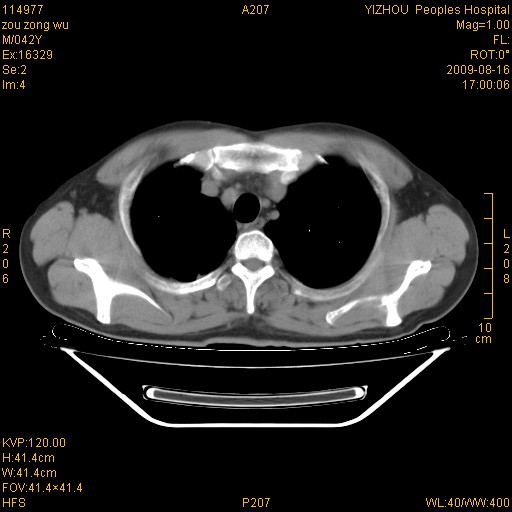

以下是引用zjzjr在2009-8-17 10:42:00的发言:[br]右侧间质性肺炎伴纤维化,右肺下叶肺囊肿伴感染(不除外外伤后引起),右肺野及胸壁软组织\\肝内见多发斑点状,中枪了吧.右侧胸膜肥厚\\粘连.